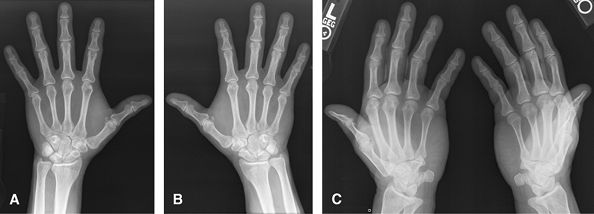

Some centers prefer pronated obliques over supinated ball

catcher (Norgaard) obliques. Both of these are good for overall

assessment of arthritis, individual erosions, soft tissue swelling, and

distribution. MRI or US are useful adjuncts to assess the soft tissues,

for synovitis joint fluid and are said to be more sensitive for

erosions.

![]() |

Figure 4 (A, B) PA of each hand. (C) AP Norgaard projection (Ball catcher’s position).